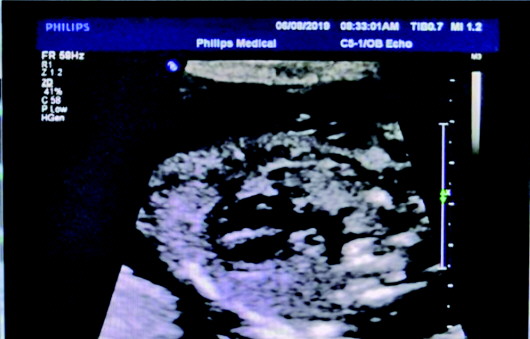

胎儿超声心脏针对性筛查。

本报6月20日讯(记者 支倩倩 通讯员 李蓓蓓) 近日,区中医院超声科省立医院专家亓恒涛教授在医院坐诊期间,筛查出一位患有心脏发育异常(肺动脉闭锁、室间隔缺损及主动脉骑跨)胎儿,填补了区中医院对于胎儿心脏相关超声筛查的技术空白。同时,也标志着区中医院超声科在胎儿畸形筛查方面迈上了新台阶。

据了解,该孕妈40岁,于孕22周在医院进行常规胎儿二级筛查,筛查期间彩超大夫发现胎儿心脏发育存在异常,让孕妈适量活动后反复检查,但因胎儿孕周偏小图像显示尚不清晰,建议孕妈预约省立医院心脏畸形筛查专家进一步检查确诊。专家确诊进一步证实了医生的判断,肺动脉闭锁合并室间隔缺损是一组严重少见的复杂多样先天性心脏病,其定义为心室与肺动脉间不存在管道连接,也无血液流通,两个心室之间间隔有缺损,严重的伴肺动脉部分或完全缺如。90%以上的患儿出生时或出生后很短时间内即出现紫绀,并呈进行性加重,85%的室间隔完整的肺动脉闭锁儿童出生后6个月内死亡,少数活到儿童期的病人主要靠较大的房间隔缺损和动脉导管未闭,极个别患儿靠较大的心外侧支循环活到成年。